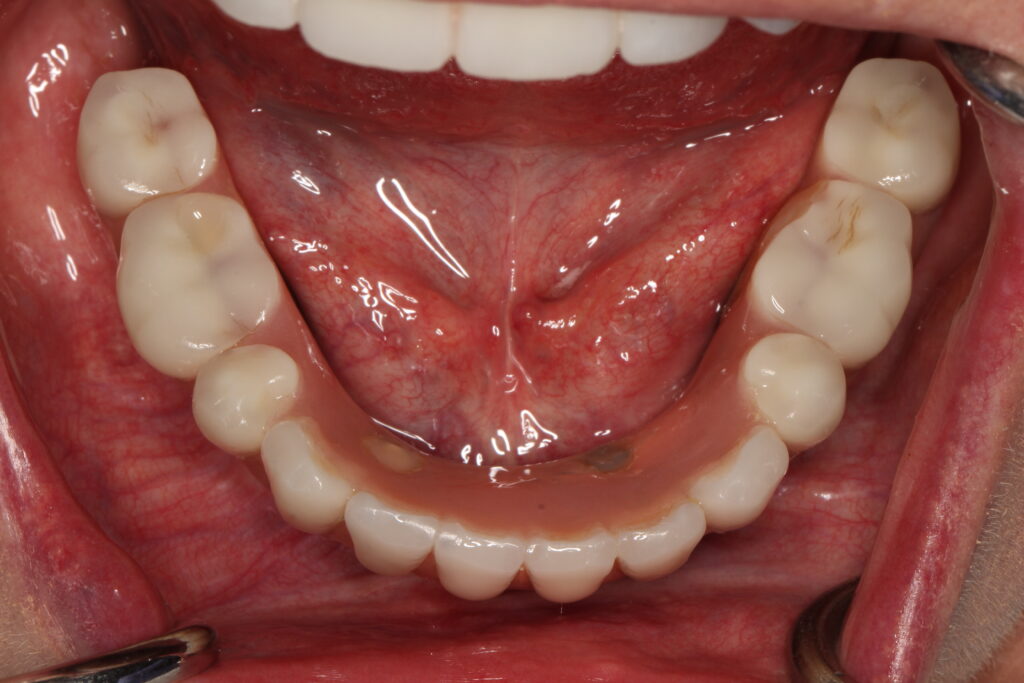

A selection of full arch fixed implant bridge patients after 5 years of wear